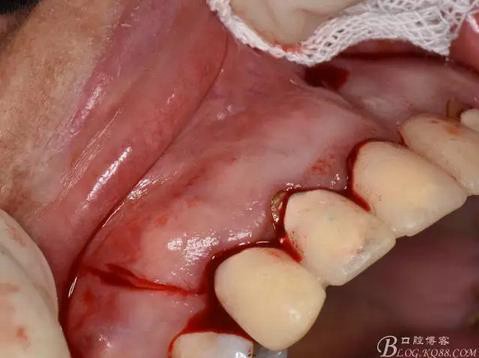

圖4.腭側(cè)觀:12根尖正對的腭粘膜隆起、有波動感

圖5.唇側(cè)局部浸潤麻醉

圖6.腭側(cè)浸潤麻醉